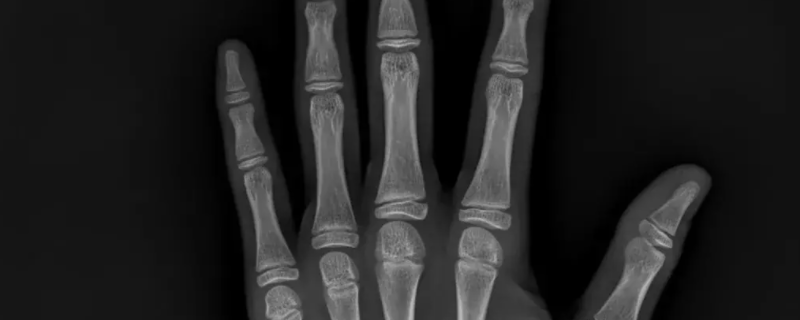

最佳答案手指测骨密度准确率不高。骨密度检查被广泛用于临床上诊断骨质疏松的患者,通过手腕关节的扫描,可以了解骨质疏松的程度,并预测病理性骨折的风险。一般情况下,骨密度检查的准确性适中,可以达到一定程度筛选、诊断的作用。但由于骨骼分布广泛,不能仅靠单一部位的骨密度检查确认骨质疏松具体程度。